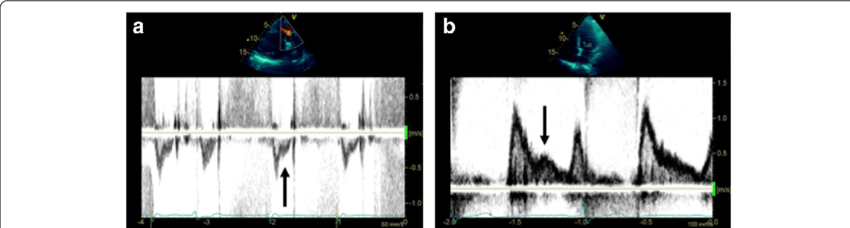

Holodiastolic flow reversal

Above the baseline

Severe aortic regurgitation

What is seen in this image?

Where is it located?

What condition is it seen in?